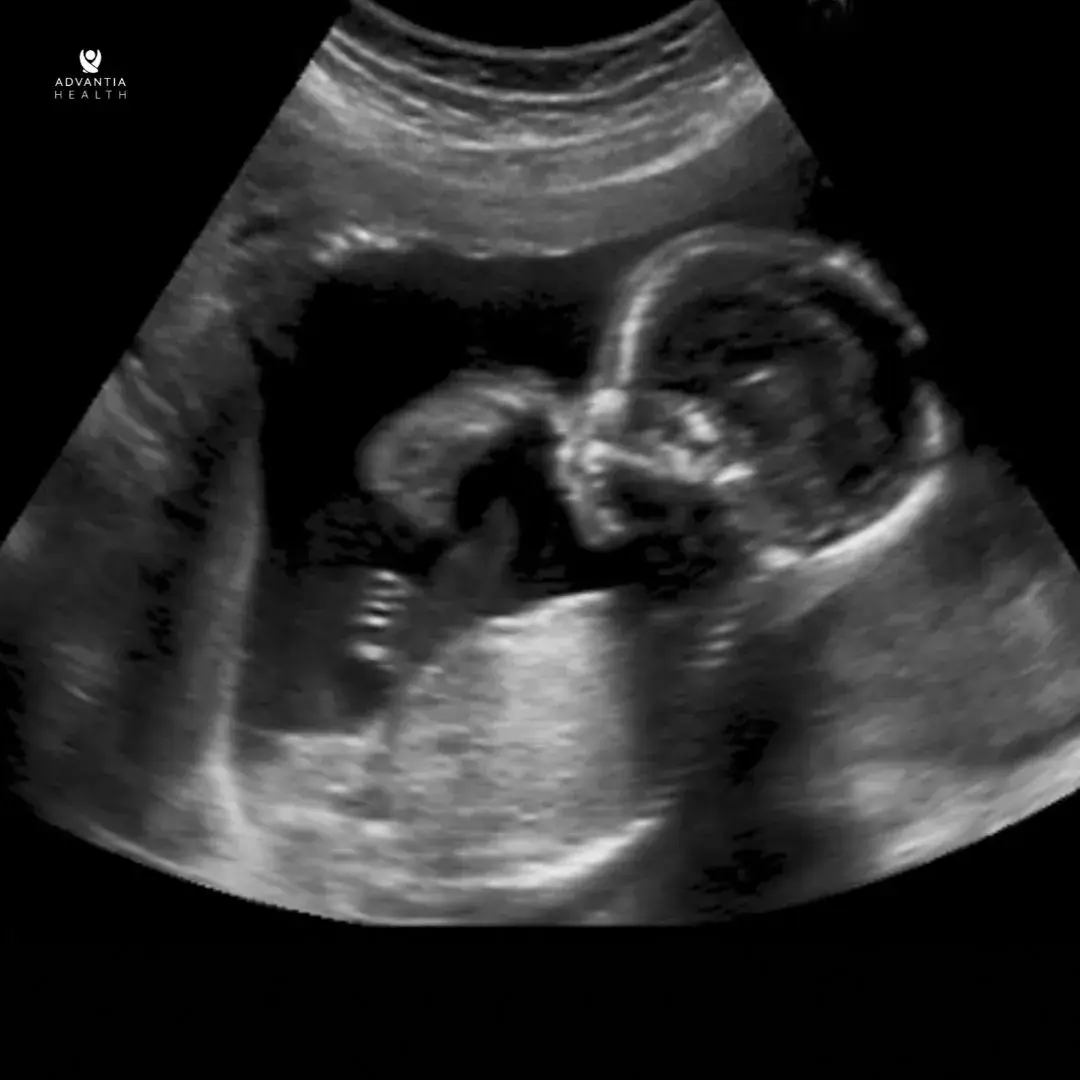

During the anatomy scan, a skilled sonographer will utilize ultrasound technology to capture detailed images of the fetus. This process involves examining various aspects, such as the baby’s head, brain, spine, heart, stomach, kidneys, bladder, and limbs. The scan will also check the fluid around the baby, placenta, and cervix position. This gives important information about how the pregnancy is going and the health of the mother and baby.